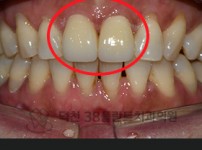

치료전후